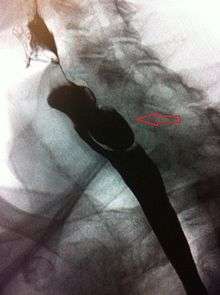

The simple barium swallow will normally reveal the diverticulum. It may also be found with upper GI endoscopy, or CT with oral contrast.

If small and asymptomatic, no treatment is necessary. Larger, symptomatic cases of Zenker's diverticulum have been traditionally treated by neck surgery to resect the diverticulum and incise the cricopharyngeus muscle. However, in recent times non-surgical endoscopic techniques have gained more importance (as they allow for much faster recovery), and the currently preferred treatment is endoscopic stapling[4][5] (i.e. diverticulotomy with staples ). This may be performed through a diverticuloscope. Other methods include fibreoptic diverticular repair.[6]

Other non-surgical treatment modalities also exist, such as endoscopic laser, which recent evidence suggests is less effective than stapling.[7]